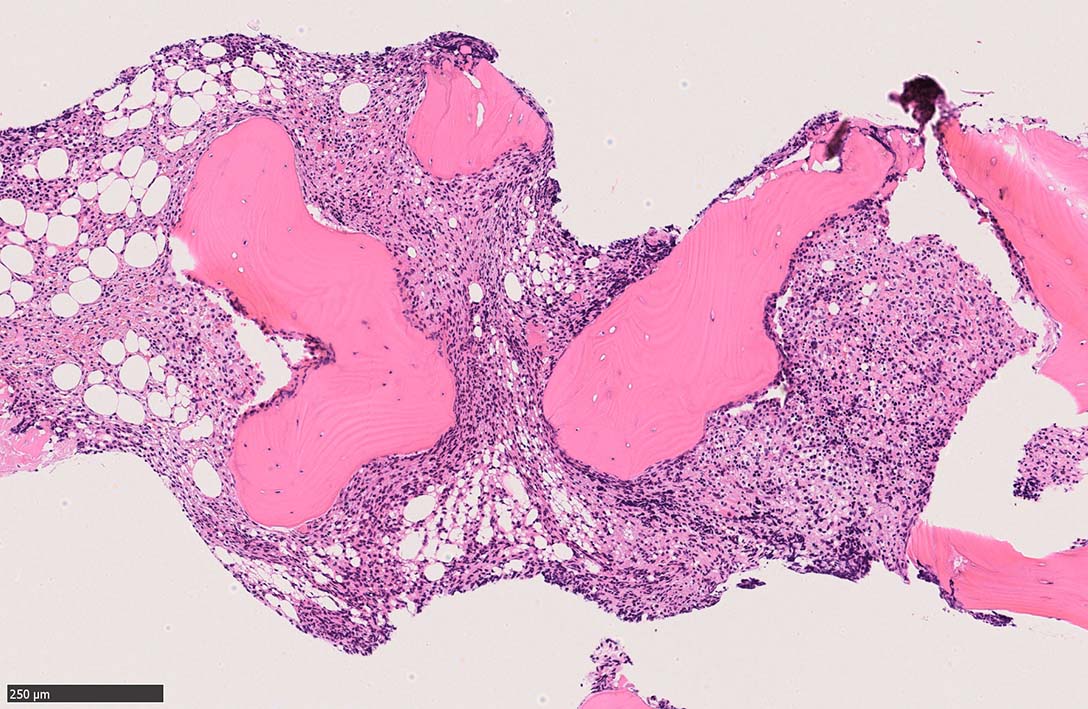

bone marrow trephine biopsy: dry tapのため骨髄生検が行われる. cellularityは40-80%とhypercellular marrow. 流れのある細胞配列は線維化を疑わせる.

ASD-Giemsa陰性の細胞がシート状に増殖する. 核はクロマチン濃染, 核小体は不明瞭.類円形, 卵円形, くびれを持つ多稜形核, 長円形いびつで屈曲した核, など多彩. 細胞質は淡清色調, 広く淡明. 赤芽球血島は幼若赤芽球のみで形成される異形成像を示す. やや離れて成熟赤芽球が疎な集簇を示す.

Ag染色では, 疎な弾性線維が増生し,増殖細胞を小胞巣状に分画するいわゆる「lymphomatoid pattern」を呈する. 本例では, Mgkに異形成所見がある.